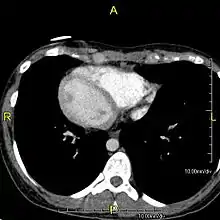

Axial CT image showing dextrocardia and situs inversus in a patient with Kartagener syndrome.

The condition affects all major structures within the thorax and abdomen. Generally, the organs are simply transposed through the sagittal plane. The heart is located on the right side of the thorax, the stomach and spleen on the right side of the abdomen and the liver and gall bladder on the left side. The heart's normal right atrium occurs on the left, and the left atrium is on the right. The lung anatomy is reversed and the left lung has three lobes while the right lung has two lobes. The intestines and other internal structures are also reversed from the normal, and the blood vessels, nerves, and lymphatics are also transposed.

If the heart is swapped to the right side of the thorax, it is known as "situs inversus with dextrocardia" or "situs inversus totalis". If the heart remains on the normal left side of the thorax, a much rarer condition (1 in 2,000,000 of the general population), it is known as "situs inversus with levocardia" or "situs inversus incompletus".